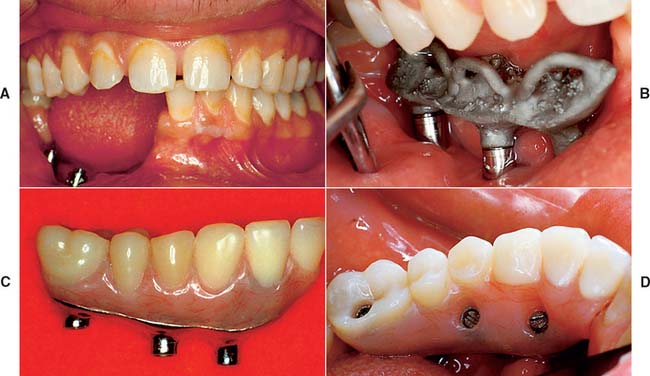

For completely edentulous patients who require nonremovable restorations, there are two implant options: a complete metal-resin fixed dental prosthesis and a metal-ceramic fixed dental prosthesis (Figs. 13-48 to 13-50).

Fig. 13-48 A to D, A metal-ceramic implant restoration may be indicated if adequate bone and soft tissue contours are available.

Fig. 13-50 Metal-resin restorations are the treatment of choice for edentulous patients with moderate bone resorption.

The complete metal-resin fixed dental prosthesis is a cast alloy framework with processed denture resin and teeth. It is typically supported by a minimum of five implants in the mandible and six in the maxilla. One major determining factor for selecting this option is the amount of bone and soft tissue that has been lost. For patients who have had moderate bone loss, the prosthesis restores both bone and soft tissue contours.

The metal-ceramic prosthesis also requires a minimum of five implants in the mandible and six in the maxilla. It can be made esthetically pleasing only if bone loss is minimal and is best suited for patients who have recently (within 5 years) lost their natural teeth. For patients with severe bone loss, there is probably only one option: a removable restoration (Fig. 13-51).